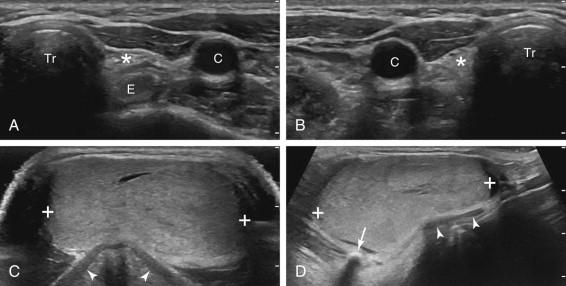

On sonography, parathyroid adenomas typically appear as variably sized, hypoechoic, homogeneous, solid masses ( Fig. 10-20 ). In some cases, the lesion is so hypoechoic that it simulates a cyst. Some internal heterogeneity and small cystic components may occur but predominantly cystic lesions are rare. Adenomas are usually oval with the long axis in the craniocaudal direction. Less often they are teardrop shaped or round. They are located lateral to the trachea or esophagus, medial to the common carotid artery, and posterior or infe­rior to the thyroid. Parathyroid adenomas are hypervascular lesions and this can often be displayed on color Doppler ( Fig. 10-21 ), although the vascularity of small lesions and deep lesions is often hard to detect with current Doppler equipment (see Fig. 10-21A ). In some cases a discrete polar artery can be visualized supplying the adenoma from the superior or inferior pole ( Fig. 10-21D ). Although detection of vascularity is reassuring, failure to detect internal flow does not exclude the diagnosis when the gray-scale findings are otherwise consistent with a parathyroid adenoma. Box 10-2 summarizes the appearance of parathyroid adenomas.

F igure 10-20, Parathyroid adenomas (cursors) in different patients. A, Transverse view shows a small, solid, hypoechoic adenoma posterior to the thyroid gland (T) and between the esophagus (E) and the common carotid artery (C) and internal jugular vein (J). B, Longitudinal view shows a small, ovoid, solid, hypoechoic adenoma posterior to the lower pole of the thyroid gland (T). C, Longitudinal view shows a moderate-sized ovoid, solid, hypoechoic adenoma posterior to the mid portion of the thyroid gland. D, Longitudinal view shows a large, ovoid, solid, hypoechoic adenoma posterior to the upper pole of the thyroid gland.

F igure 10-21, Vascularity of parathyroid adenomas (cursors) in different patients. Color Doppler views in three different adenomas show no detectable vascularity (A) , moderate vascularity (B) , and hypervascularity (C) . D, Dual color Doppler and gray-scale views show hypervascularity with a prominent polar vessel (arrow) .

Ectopic locations are encountered in approximately 3% of patients ( Box 10-3 ). The retrotracheal region is a common site for ectopic superior adenomas. These can be difficult to visualize sonographically due to their deep location and gas shadowing from the trachea. To counteract this, the patient's head should be turned to the opposite side and scanning should be performed from a lateral location with the transducer angled medially. Lower-frequency curved-array probes with a short radius of curvature are also helpful in detecting deep adenomas. Probes designed for neonatal heads or transvaginal scanning are very small and often work very well in looking deep into the neck ( e-Fig. 10-5 ). Ectopic parathyroid adenomas can also be located in the carotid sheath ( Fig. 10-22 ) or in the thyroid ( Fig. 10-23 ). Intrathyroidal adenomas are easy to see sonographically but can be easily confused with thyroid adenomas or other thyroid nodules. They can occur in any part of the thyroid but are usually located in the posterior half. They have sonographic features similar to other parathyroid adenomas. The superior mediastinum is a well-recognized but very uncommon location for ectopic adenomas. When in the mediastinum, they are usually anterior and related to the thymus, although they can occur posteriorly and as low as the aortopulmonary window. Mediastinal adenomas are difficult to visualize with sono­graphy because high-frequency linear-array transducers that are typically used have limited penetration and are often too large to manipulate in the relatively confined suprasternal and supraclavicular regions. As with deep lesions in the neck, tightly curved array probes can assist in visualizing superior mediastinal adenomas ( Fig. 10-24 ). Approximately 5% of patients with hyperparathyroidism have multigland disease ( e-Fig. 10-6 ). Multigland involvement is considerably more difficult to detect with all imaging modalities.

F igure 10-22, Ectopic parathyroid adenomas (cursors) in the carotid sheath in different patients. Longitudinal (A) and transverse (B) views of the neck show a parathyroid adenoma located in the sheath of the common carotid artery (C). C, Transverse view of the carotid bifurcation shows a parathyroid adenoma located immediately adjacent to the external (E) and the internal (I) carotid arteries.

F igure 10-23, Intrathyroidal parathyroid adenomas (cursors) in different patients. A, Transverse view shows a small adenoma in the posterior aspect of the thyroid that was partially intrathyroidal at surgery. B, Longitudinal view of the thyroid shows an intrathyroidal adenoma located in the mid aspect of the gland. Aspiration of this nodule yielded follicular cells consistent with either thyroid or parathyroid origin. The parathyroid hormone level of the aspirated material was 4423 pg/mL. C, Transverse view shows a parathyroid adenoma in the anterior aspect of the thyroid.